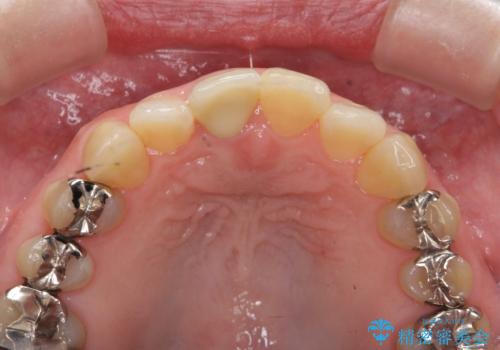

- 十数年前に治療した前歯のクラウンの歯ぐきの位置が変化し、黒いラインが見え審美性の改善を求めて来院されました。

ファイバーコアのやりかえを行ったのち、金属を用いないジルコニアクラウンによる再補綴を行い前歯の審美性の向上を計画します。

近年前歯のクラウン製作に用いられるジルコニアクラウンは、金属を用いていないため経年的に歯ぐきの位置が変わっても黒いラインが見えることなく審美性の意地が期待できます。